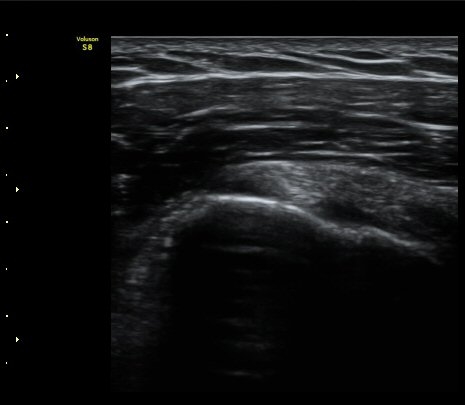

ÀÌµÎ¹Ú±Ù°Ç È¾´Ü¸é°Ë»ç¿¡¼­ ƯÀÌ ¼Ò°ß ¾øÀ½

(no specific abnormal findngs with transverse scan of biceps tendon) »çÁø 1, 2